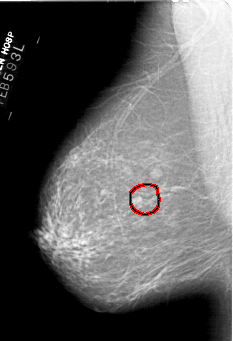

A_1443_1.RIGHT_MLO

RIGHT_MLO LINES 5956 PIXELS_PER_LINE 3916 BITS_PER_PIXEL 12 RESOLUTION 43.5 NON_OVERLAY

FILE: A_1443_1.LEFT_CC.OVERLAY

TOTAL_ABNORMALITIES 1

ABNORMALITY 1

LESION_TYPE MASS SHAPE OVAL MARGINS ILL_DEFINED

ASSESSMENT 4

SUBTLETY 3

PATHOLOGY BENIGN

TOTAL_OUTLINES 1

BOUNDARY